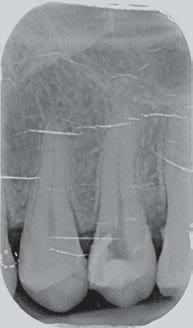

This element was not stimulated with the cold test and the radiographic image revealed an incomplete endodontic treatment (Figs. 1-2). The element seemed to present a suitable root length for a conservative restoration, but the apical position of the carious lesion and the proximity of the interdental bone ridge didn’t allow a correct rehabilitation with prosthetic crown, respecting the biological width.2

Figure 2: Initial radiograph showing endodontic dressing that had been present for some months, but the treatment was never completed. Note the depth of the caries lesion and the proximity of the interdental bone ridge, which may represent an obstacle for prosthetic rehabilitation.